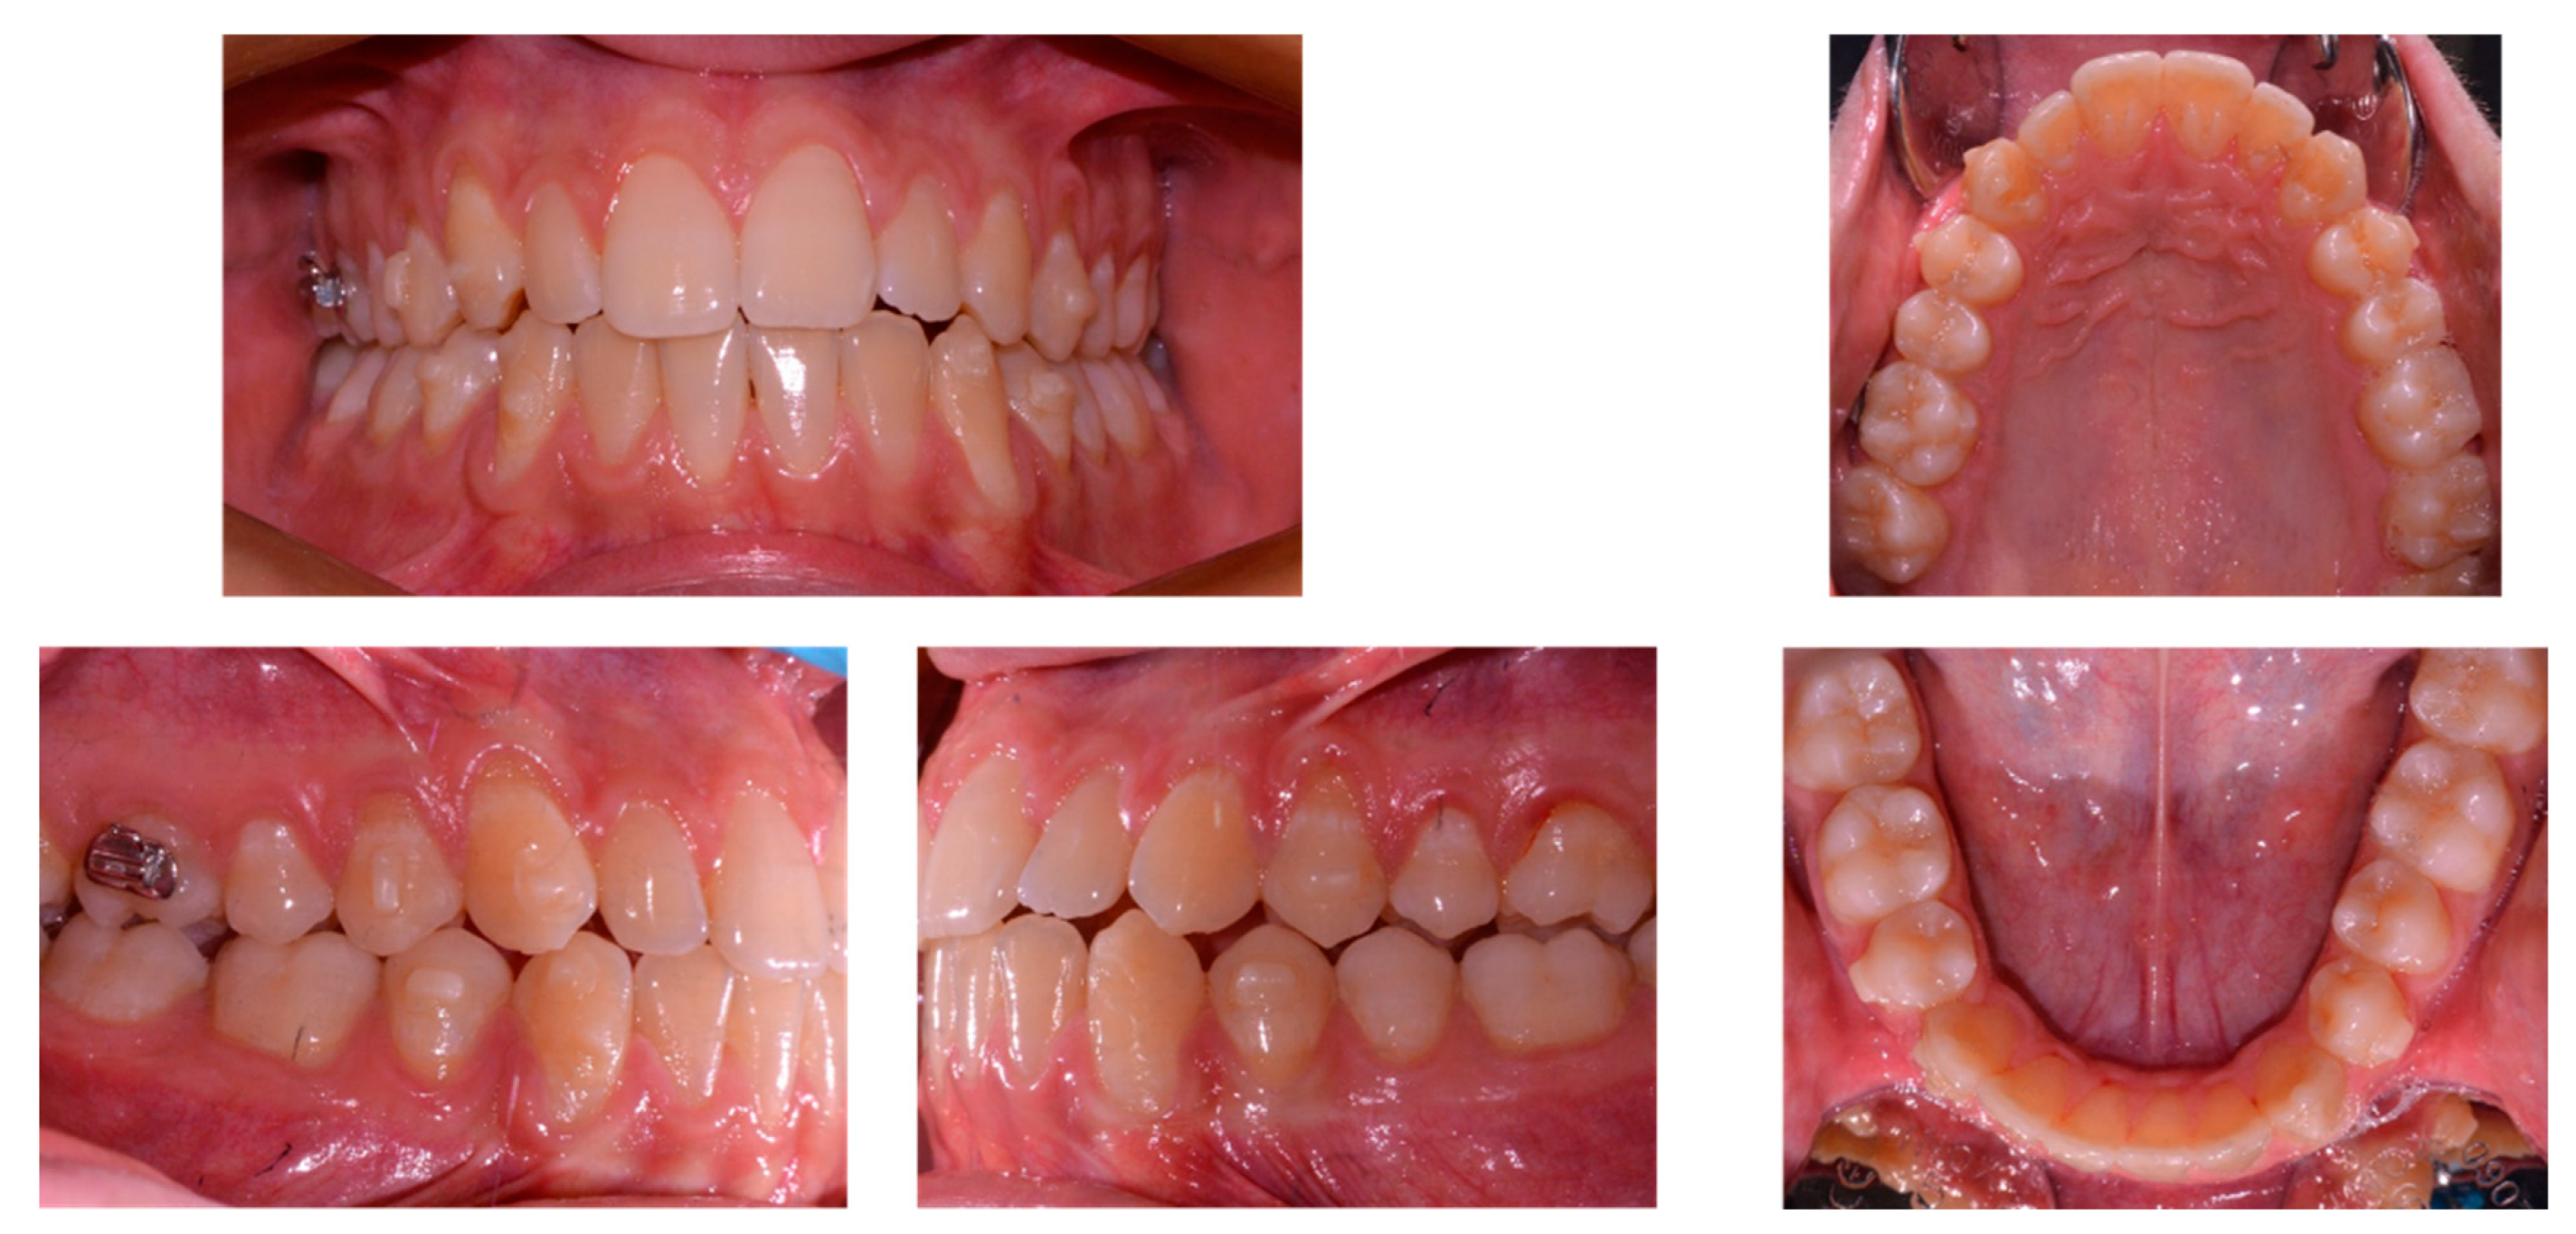

| Measurements | Initial | Final | Norm |

|---|---|---|---|

| SNA (°) | 86.7 | 87.5 | 82.0 ± 3.5 |

| SNB (°) | 84.1 | 84.9 | 80.0 ± 3.5 |

| ANB (°) | 2.6 | 2.6 | 2.0 ± 2.5 |

| SN^ANS-PNS (°) | 7.2 | 6.3 | 8.0 ± 3.0 |

| SN^GoGn (°) | 37.7 | 37.7 | 33.0 ± 2.5 |

| ANS/PNS^Go-Gn (°) | 33.3 | 33.3 | 25.0 ± 6.0 |

| U1^ANS-PNS (°) | 113.2 | 111.8 | 110.0 ± 6.0 |

| L1^GoGn (°) | 85.1 | 80.4 | 90.0 ± 6.0 |

| L1 Protrusion (L1-APo) (mm) | 1.6 | 1.3 | 1.0 ± 2.5 |

| Overjet (mm) | 2.6 | 2.4 | 2.5 ± 2.5 |

| Overbite (mm) | 0.6 | 1.5 | 3.0 ± 2.5 |

| U1^L1 (°) | 131.1 | 136.4 | 135.0 ± 6.0 |

| Co-Go-Me (°) | 123.9 | 124.8 | 125.0 |

| Lower lip to Ricketts E-line (mm) | −4.8 | −5.6 | 0.0 ± 2.0 |